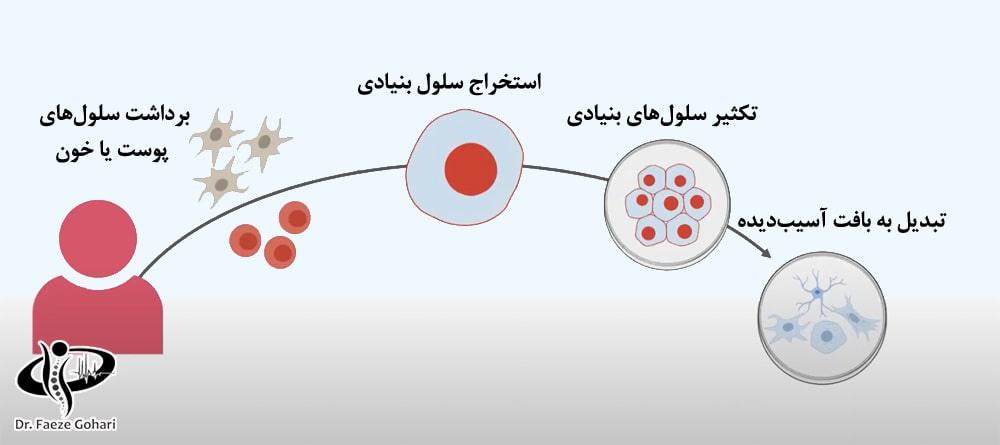

در درمان با سلولهای بنیادی، پیآرپی (پلاسمای غنی از پلاکت) و سلولهای بنیادی به طور مشترک و بهصورت یک کوکتل تزریقی استفاده میشوند. پیآرپی با تحریک و تسریع روند بازسازی سلولهای بنیادی، نقش مؤثری در کاهش التهاب دارد و به تسریع بهبود بافتها کمک میکند. علاوه بر این، پیآرپی میتواند درد ناشی از تزریق را کاهش دهد و فرایند درمان را راحتتر کند. فرایند تزریق شامل مراحل زیر است.

تهیه سلولهای بنیادی از بانک سلولی معتبر

معمولاً سلولهای بنیادی بهصورت ویالهای آماده از بانکهای سلولی معتبر تهیه میشوند، چرا که این روش امکان دسترسی به حجم بیشتری از سلولهای بنیادی باکیفیت بالا را فراهم میآورد.